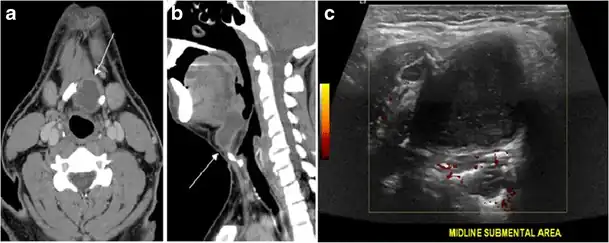

Fig. 8. A 48-year-old male patient post total thyroidectomy with PTC recurrence. a Transverse greyscale ultrasound of the neck demonstrates a left thyroid bed heterogeneous, predominantly hypoechoic irregular lesion with calcifications (white arrow). b A spot image of iodine 123 total body scan of the neck demonstrate a focus of abnormal radiotracer uptake at the left thyroid bed (Black arrows) between the annotated markers. c Enhanced axial CT scan of the neck demonstrates an enhancing large left thyroid bed mass (white arrow) with no calcifications. The lesion exerts a mass effect on the oesophagus (black arrow) and is inseparable from the trachea.[1] -